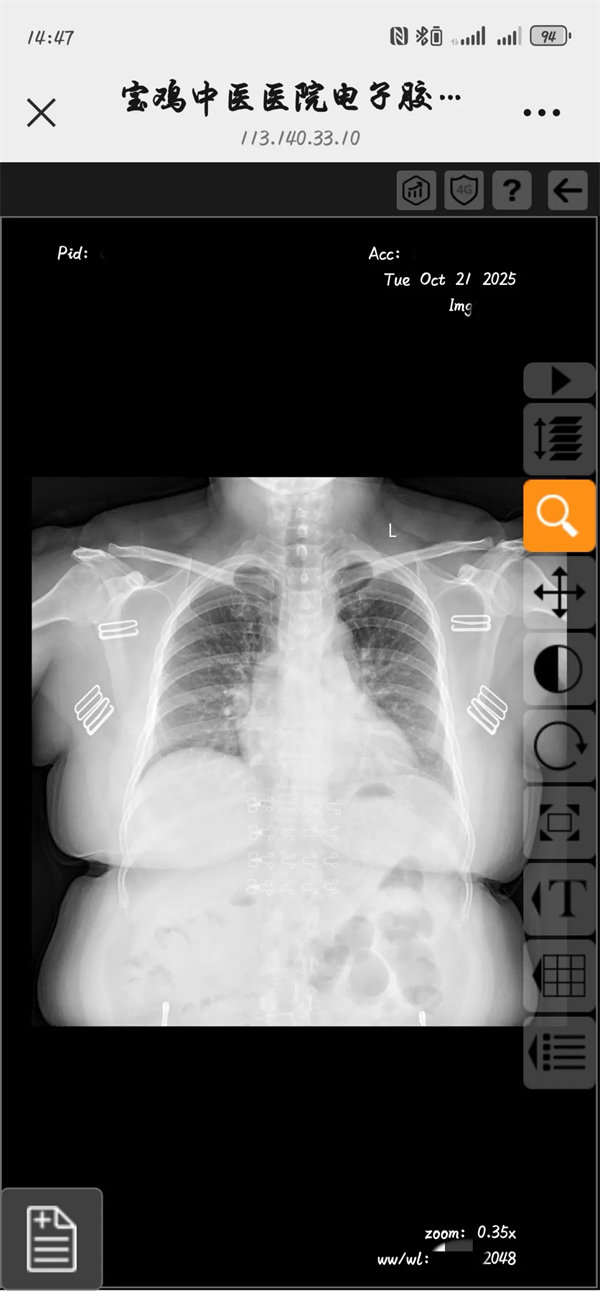

“别愁啦,从现在起,‘云胶片’正式上线啦!无需再领取传统X光、CT、MR等胶片,通过手机即可查看和分享,影像检查报告及高清图像啦!”

家人们!以后去医院做影像检查,再也不用抱着一沓沉甸甸的胶片到处跑啦!担心胶片折了、丢了,下次复诊找不到还得重新拍?这些让人头大的麻烦从今天起彻底说再见!我院‘云胶片’已正式上线,不管是X光、CT还是MRI,检查结束后,报告和影像按规定时间同步到‘云端’,你只用打开手机就能轻松查看。想存多久存多久,复诊时给医生扫码就能调阅,轻便又安心,就医体验直接拉满~